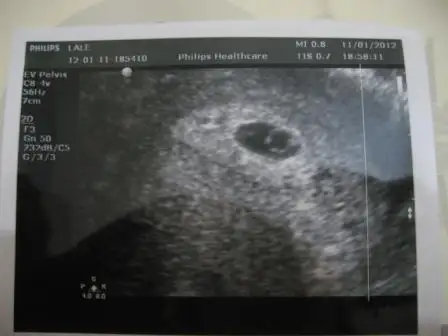

dün doktora gittim kızlar...işte bu benimki... keseyi gördüm ve kalp atışları duydum

.... doktorda tek taşa benziyor dedi

doktor tam 6 haftalık dedi ... bebek 3,7 mm![]()